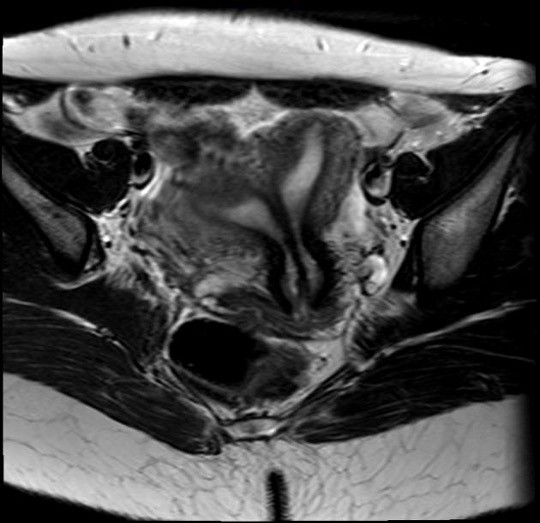

32세 여성이 난임으로 내원하였다. 과거에 세 번의 자연유산이 있었다. 남편의 정액 검사 결과는 정상이었다. 골반 MRI 및 자궁나팔관조영 검사 결과이다. 치료는?

• MRI상 자궁은 부피가 크고 앞쪽으로 기울어져 있으며, 두 개의 자궁강이 septum(low signal density로 보이고 있음)로 나뉘어 있다. 이 저신호는 자궁경부까지 뻗어 있으며, fundus의 평평한 윤곽이 관찰된다. 이는 완전 중격자궁(complete septate uterus)을 시사한다. 쌍각자궁의 경우 fundus에서 1cm 이상으로 깊게 함입되어 있다.